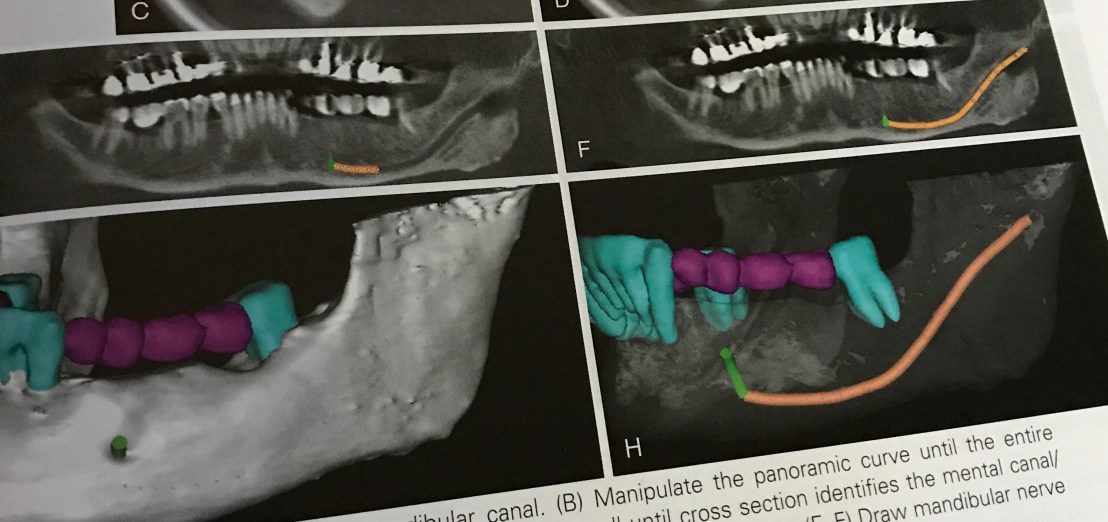

ตัวอย่างของการอ่านภาพ CBCT

รูป A และ B คือการใช้ Panoramic view หา Man. canal

รูป C และ D ใช้ Cross section view จนพบ Mental foramen ลูกศรเขียวคือ path ของ Mental nerve

รูป H คือ การวาด path ที่สมบูรณ์ของ Inf alv nerve, Mental foramen และ ตำแหน่งการวาง Prosthesis